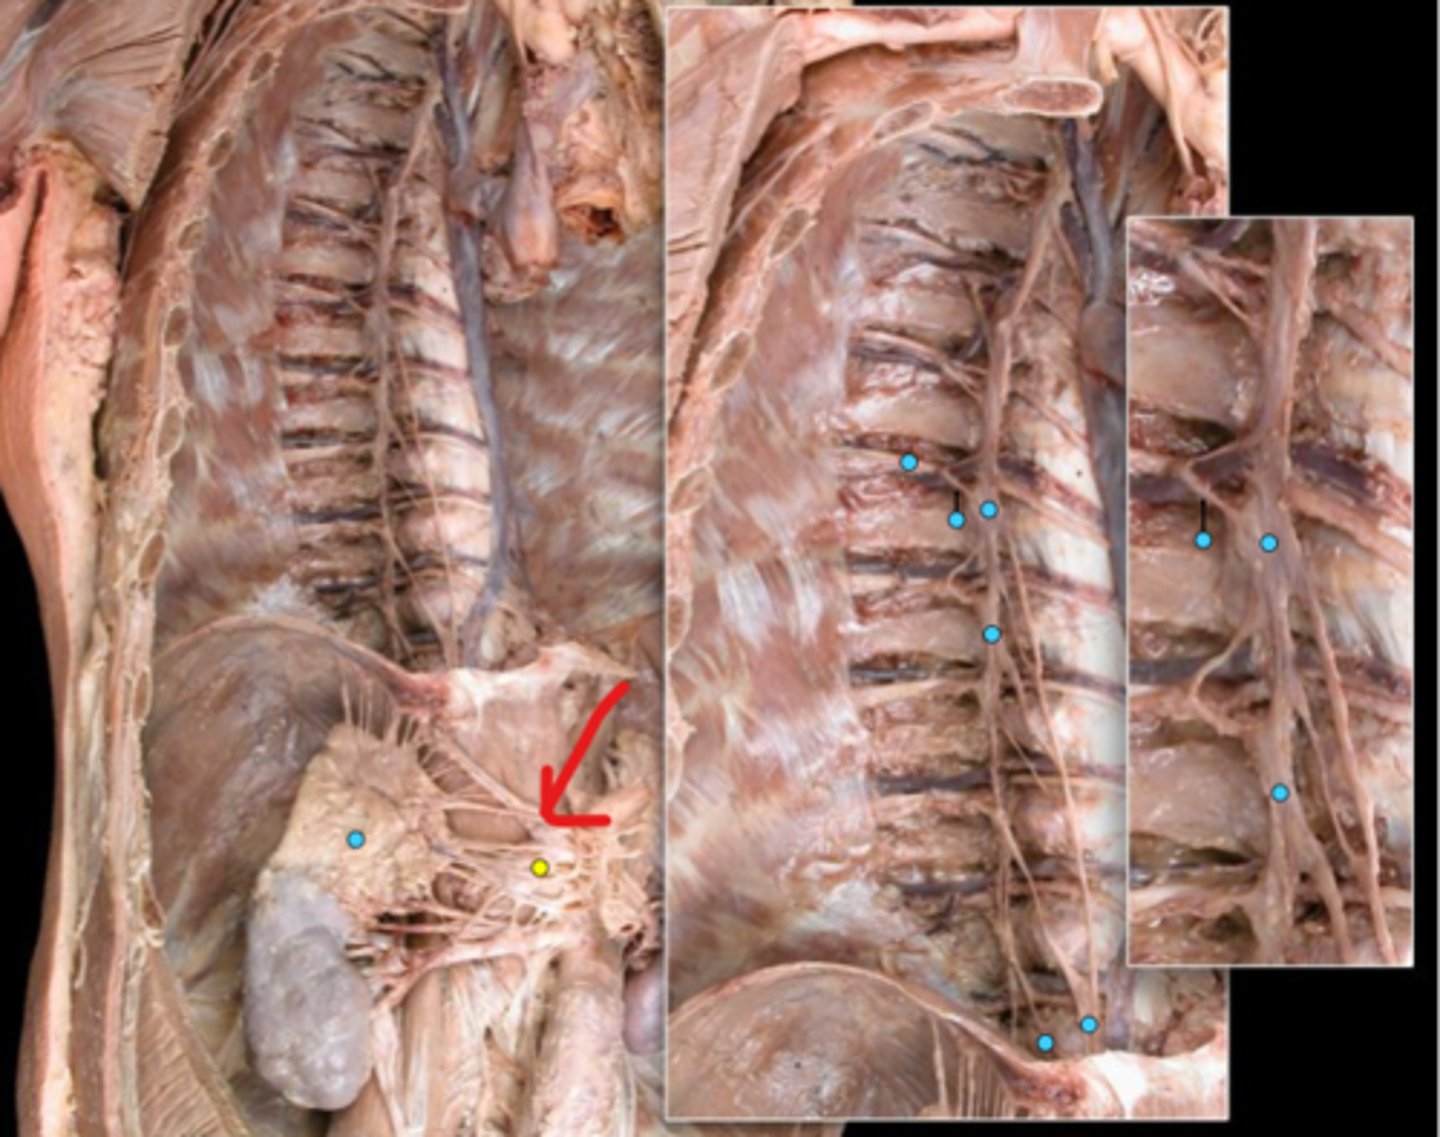

Suprarenal gland

Celiac ganglion

Intercostal nerve

Communicating ramus

Sympathetic trunk ganglion

Sympathetic trunk

Lesser splanchnic nerves

Greater splanchnic nerve

Anterior (ventral) ramus

Spinal nerve trunk

Posterior (dorsal) ramus

Spinal ganglion